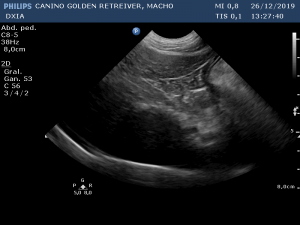

Última Imagen Hepática DXIA Scott

Última Imagen Hepática ante último ciclo de quimio